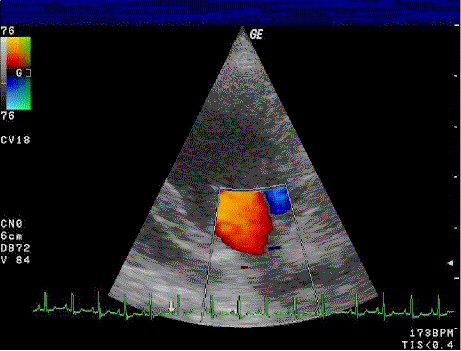

심장 초음파 검사는 승모판 역류(MR)의 진단을 확인하는 데 일반적으로 사용된다.[16] 경흉부 심장 초음파(TTE)에서 컬러 도플러 혈류 검사는 심실 수축기 동안 좌심실에서 좌심방으로 혈액의 제트가 흐르는 것을 보여준다. 또한 확장된 좌심방과 심실, 그리고 감소된 좌심실 기능을 감지할 수 있다.[11] 필요한 경우, 심장의 뒤쪽도 볼 수 있으므로 경식도 심장 초음파 검사(TEE)로 더 선명한 영상을 얻을 수 있다.[17]